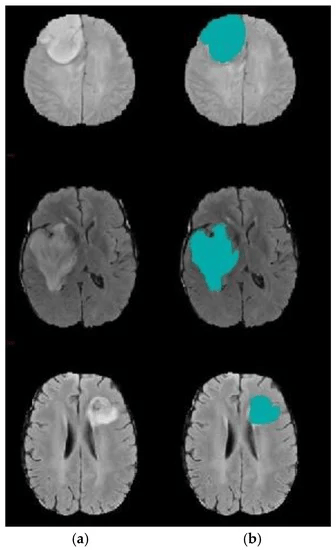

NUMBER_OF_CLASSES = 2Binary Segmentation